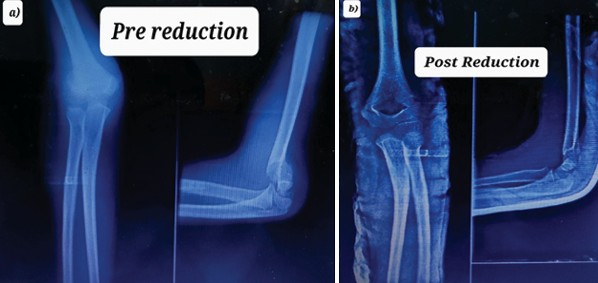

Window is made volarly at the wrist area (Fig. 4a) and integrity of radial pulse confirmed (Fig. 4b). Arm sling applied (Fig. 4c). Child is sent to X-ray (Fig. 5). Post confirmation of reduction in X-ray, patient was prescribed analgesics and advised limb elevation and active movement of fingers in home.

Figure 5: X-rays (a) Pre reduction, (b) Post reduction.